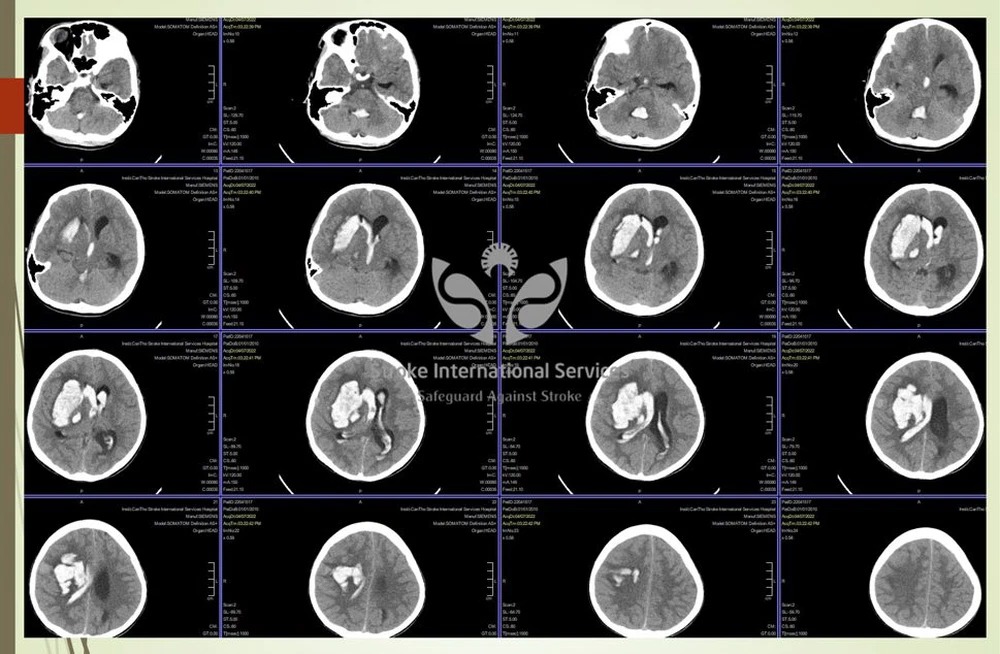

Thông tin trên Tổ Quốc, bệnh nhi vào cấp cứu tối 7/4 với biểu hiện đau đầu dữ dội kèm theo nôn ói. Khi vào viện bác sĩ đã nghi ngờ xuất huyết não do vỡ phình mạch máu não.

Với các trường hợp chảy máu não, việc điều trị khó là tuỳ vào lượng máu chảy, vị trí xuất huyết, tình trạng lâm sàng lúc nhập viện có còn cơ hội để cứu chữa hay không. Cấp cứu các trường hợp này thời gian vẫn là yếu tố vô cùng quan trọng.

Khi xảy ra đột quỵ ở trẻ em, thì ngày nay sẽ điều trị theo phương pháp can thiệp nội mạch DSA, ít xâm lấn, đặc biệt là điều trị được những vùng não sâu mà phẫu thuật không mổ tới. Ngoài ra, sau can thiệp trẻ nhỏ bảo tồn được phần lớn chức năng, không để lại bất kỳ vết sẹo nào.

Di dạng mạch máu não là bệnh nguy hiểm nhưng nếu được chẩn đoán sớm có thể điều trị khỏi hoàn toàn. Hiện nay, phương pháp chụp mạch máu não bằng ứng dụng DSA giúp bác sĩ có cái nhìn chính xác về vị trí, kích thước, hình dạng của đoạn mạch dị dạng đồng thời vẽ được biểu đồ huyết mạch nơi mạch máu dị dạng phát sinh.